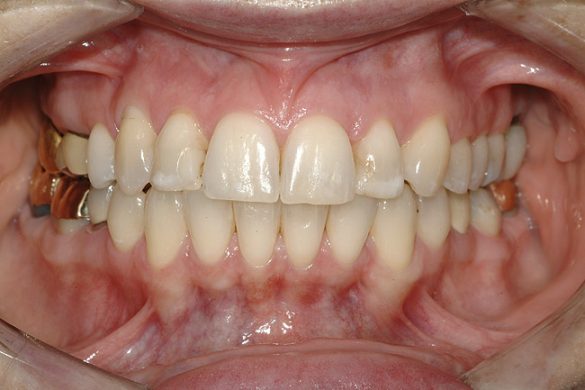

ETAPA aII-a: ORTODONŢIE COMPREHENSIVĂ

Pacienta a fost îndrumată pentru evaluarea ortodontică comprehensivă. Aşteptările tratamentului constau în nivelarea planului ocluzal maxilar, corectarea rotaţiilor şi a angrenajelor inverse şi alinierea dinţilor, cu îmbunătăţirea nivelurilor şi funcţiilor tisulare. Obiectivul primar al terapiei ortodontice era stabilirea poziţiei dentare ideale pentru tratamentul restaurator (fig. 10- 12).

Pentru această pacientă s-a recomandat ortodonţia cu scopul de a minimiza cantitatea de preparaţie dentară necesară în cazul în care dinţii rămâneau aliniaţi în malpoziţie. Dintr-o poziţie comprehensivă de planificare a tratamentului, reducerea masivă a structurii dentare slăbeşte dintele, amplificând astfel riscul biomecanic al pacientului, cu reducerea prognosticului pe termen lung5. Un rezultat estetic acceptabil este, de asemenea, mai puţin predictibil când se restaurează dinţi malpoziţionaţi.